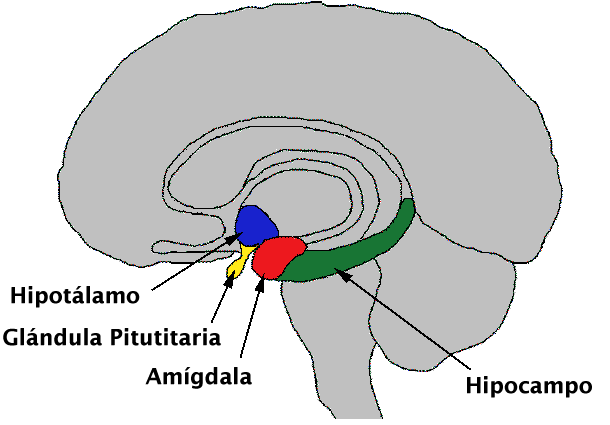

Situado en el lóbulo temporal cerca del uncus. Se considera parte del sist. límbico. NÚCLEO AMIGDALINO Puede influir en la respuesta del organismo a los cambios ambientales. Por ejemplo, en la sensación de miedo (frec. cardíaca, presión, color de piel, frec. respiratoria).